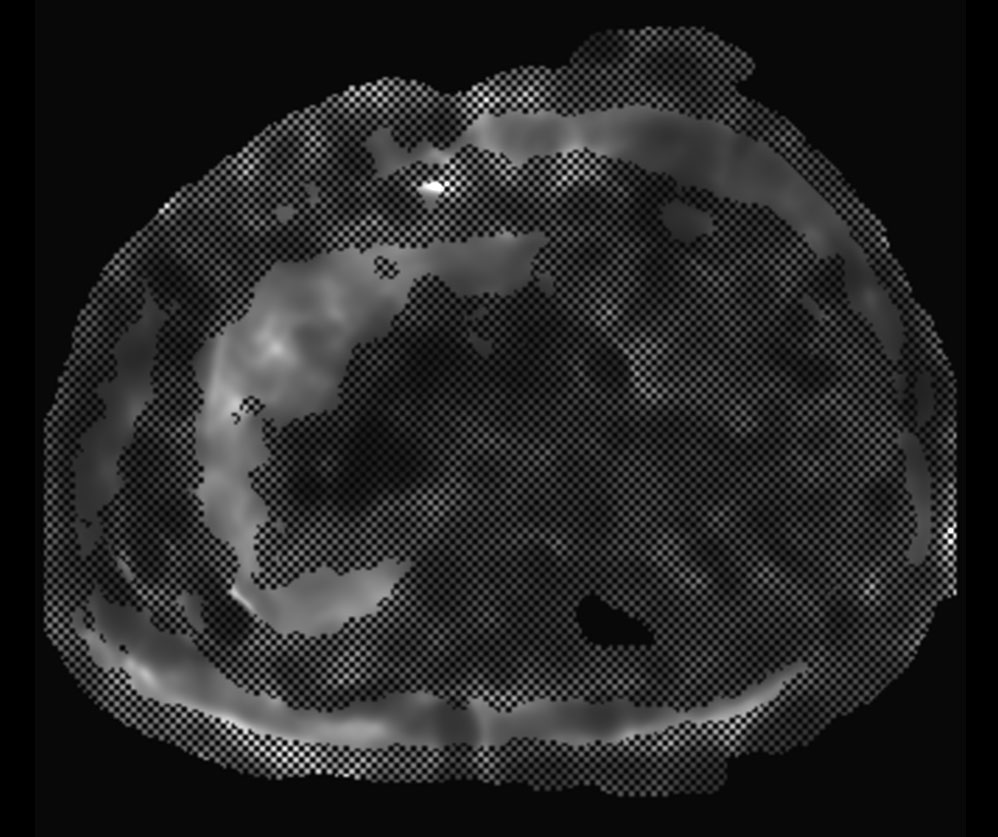

MR Elastography (confidence map) SE-EPI, 13 sec BH/4 slices

MR Elastography (confidence map) SE-EPI, 14 sec BH/8 slices